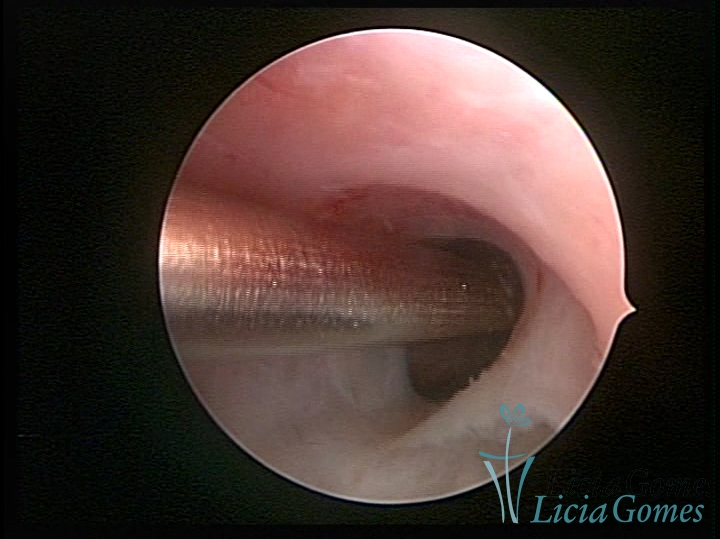

FIBROUS SYNECHIA

Uterine synechiae are scars (adherence) between the surface of the uterine walls, which may occur after the surgical procedure, uterine curettage, or after an inflammatory process in the uterine cavity (endometritis), which may lead to menstrual changes, infertility and obstetric complication such as abortion and premature birth.